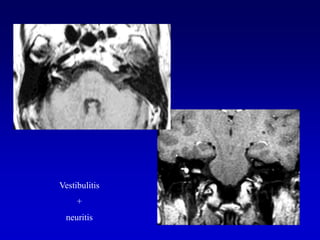

Lesión intracanalicularScreening con  T2 DRIVEExclusión con secuencias T1 Gd que son las secuencias mas sensibles para el Schwannoma intracanalicular, pero no siempre especificas, a veces es difícil la diferenciación con neuritis

Secuencias T2 (DRIVE)Secuencias T2 muy finas permiten información esencial y por lo tanto,  se usan de rutina . Ellas permiten la evaluación de  Tamaño del tumorErosión osea del CAI Neuritis vs ( nervio normal)  Schwannoma

Secuencias T2 (DRIVE)Con el T2 puede verse el LCR en el fondo de saco del CAI

*

El realce lineal fusiforme con Gd al interior del CAI puede ser ocasionado por:Pequeño Schwannoma (T2  muestran un nódulo sobre el nervio)Neuritis (T2  grosor del nervio normal)AICA normal (T2  pueden confirmar)Invasión  meníngea o hiperemia (T1 con matriz de 512 x 512  Gd pueden distinguir realce a lo largo de las paredes del CAI en vez del centro del CAI)

Vestibulitis+neuritis